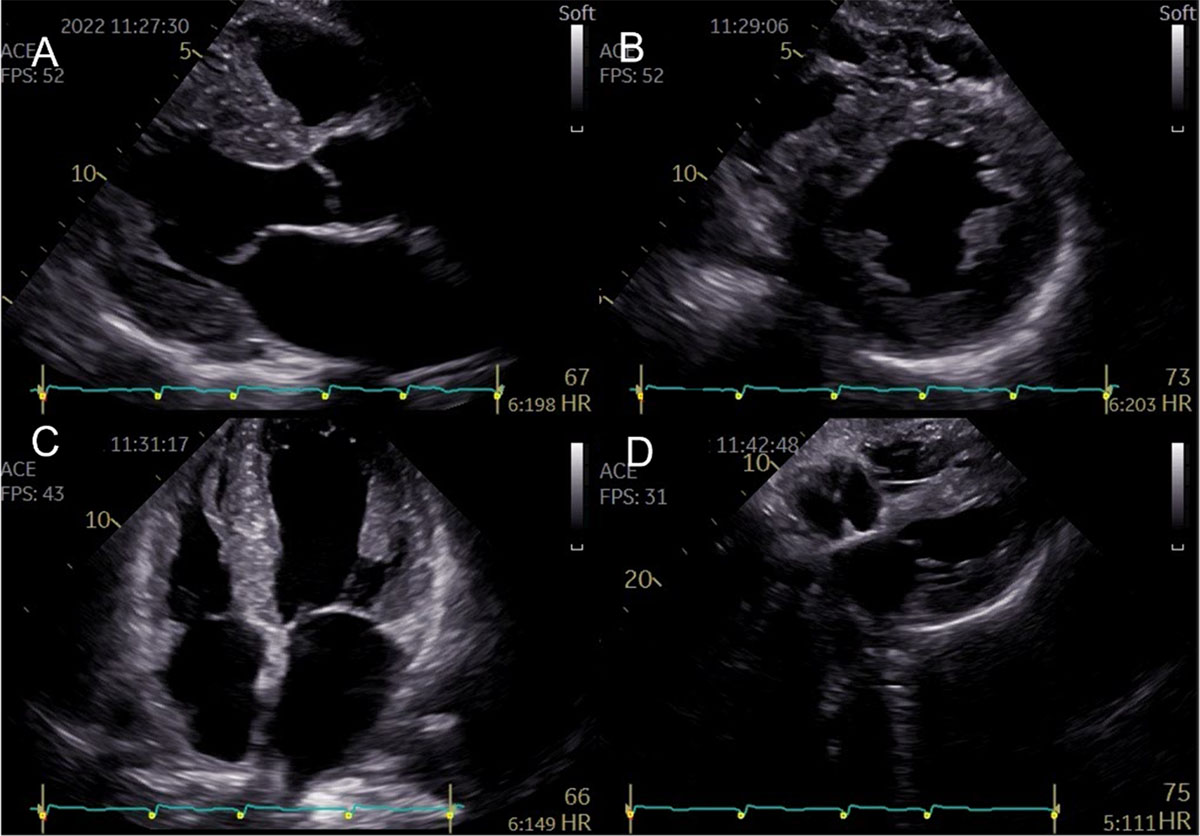

Figure 2

Representative two-dimensional echocardiographic findings of cardiac amyloidosis in a patient with ATTR-CM. (A) Parasternal longitudinal view (B) Short axis view (C) Apical 4-chamber view (D) Subcostal view Concentric left ventricular and right ventricle free wall hypertrophy, thickened interatrial septum, and atrioventricular valves. (Images courtesy of Centro Hospitalar Universitário Lisboa Norte, Lisboa, Portugal).